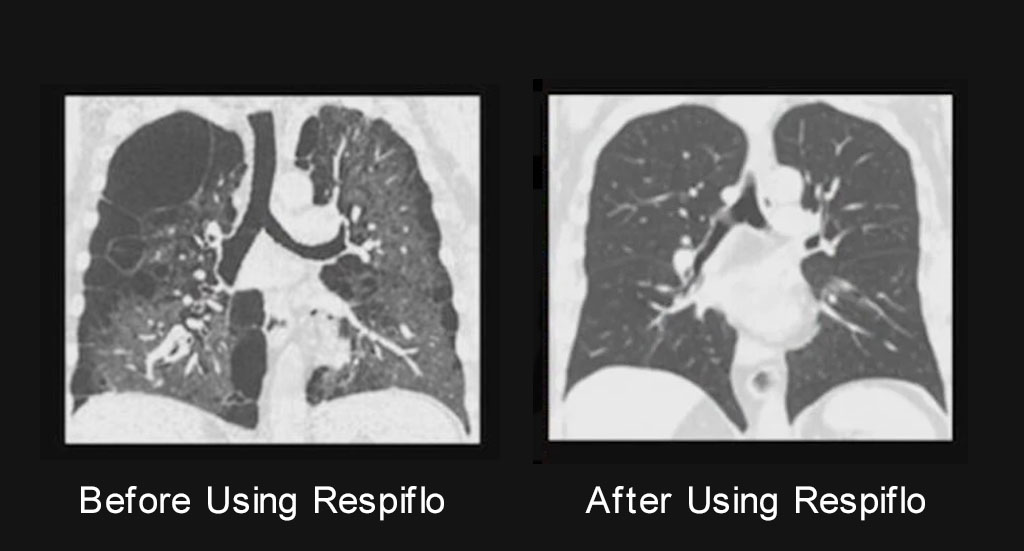

A few months ago my COPD symptoms were really limiting my daily life. Climbing stairs or carrying groceries would leave me struggling to catch my breath. My doctor ordered a chest X-ray, and when he showed it to me, the areas of congestion and reduced airflow were pretty obvious. Fortunately, tha'ts when I started following the routine and stuck with it every day. I chose the full 6 month treatment, but just after 7 weeks, I noticed my chest didn’t feel as heavy and I could take fuller breaths. At my next checkup, another X-ray was taken. My doctor said my lungs appeared less congested than before and my breathing capacity seemed improved during testing.

A few months ago my COPD had gotten so bad I could barely climb the stairs without stopping. My doctor showed me my lung X-ray and said my lungs looked pretty congested. It honestly scared me. I ordered the 4 bottle discounted offer and started doing the breathing method from the video every day. A few weeks later I went back for another checkup and when my doctor was shocked when he saw the new X-ray. My lungs looked much clearer, and I could really feel the difference in how much easier it is to breathe now.